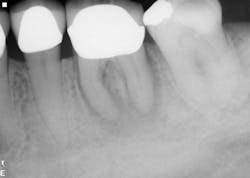

Healing is noted on the six-month follow-up (figure 4).